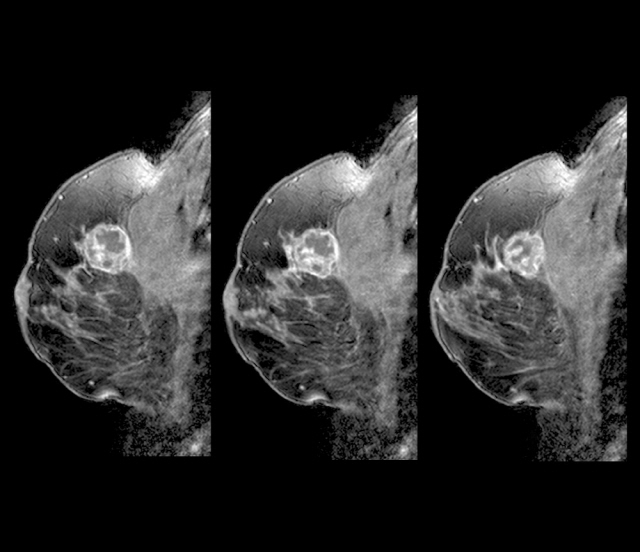

유방 검사 중 유방엑스레이로 인한 유방 촬영 시 유선은 하얗게, 지방은 검게 표현되는데 치밀유방은 유선조직의 양이 더 많기에 전반적으로 하얗게 나와 엑스레이로 한 유방촬영만으로는 정확한 유방 검사 결과를 얻기가 어렵습니다.이러한 치밀유방은 유방에 특별한 이상이 있는 것은 아니지만, 유방엑스레이만으로는 정확한 검사 결과를 얻기 어려워 유방종양 분별이 힘들기 때문에 유방 검진 시 정확한 결과를 얻기 위해 유방초음파 검사를 추가적으로 받는 것을 권해드립니다.치밀유방 기준 및 단계에 대해서치밀유방은 유선조직의 밀도에 따라 크게 1~4단계로 분류됩니다. 치밀유방 단계

3단계와 4단계가 치밀유방에 해당하며, 이 단계에 해당할 경우 유방엑스레이 촬영 시 방사선이 유선조직을 투과하지 못하기 때문에 유방종양을 확인하기가 어려워 유방초음파 검사 등 추가적인 검진이 필요합니다. 치밀유방 원인은?